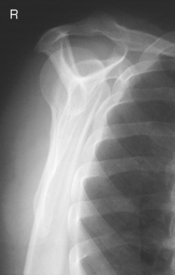

Posterior oblique (Grashey method) (S)

Posterior oblique (Grashey method) critique